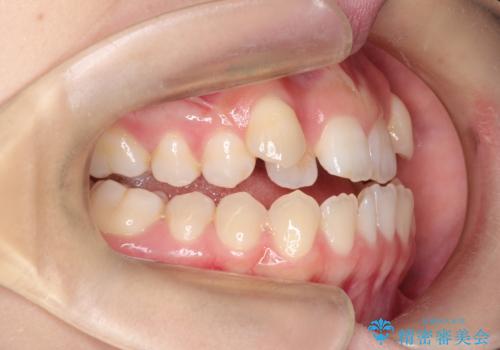

MARPEで非抜歯矯正|オープンバイトと八重歯を改善

- 治療計画

上顎にTAD(矯正用アンカースクリュー)を設置し、MARPEにより骨格レベルで上顎の幅を拡大。数週間の拡大期間を経て十分なスペースを確保したのち、マウスピース型矯正装置(インビザライン)で歯列全体を整えました。八重歯もアーチ内に自然に収まり、非抜歯で審美性と機能性を両立。治療後は「噛み合わせが安定して笑顔に自信が持てるようになった」とご本人にも大変満足していただきました。